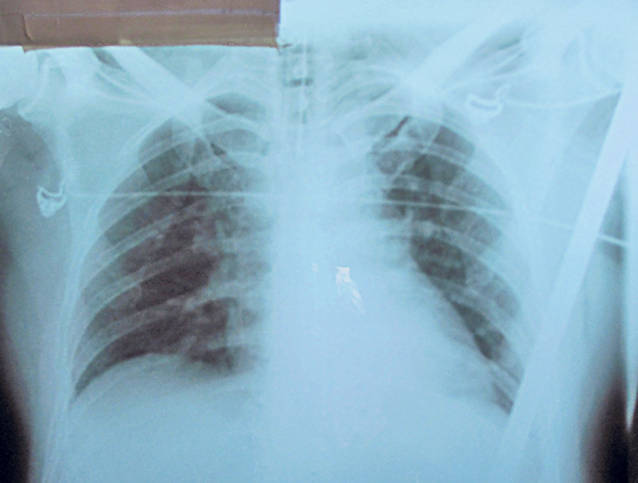

“Bucata de fier i-a provocat o plagă, intrarea fiind în zona inghinală dreaptă, aproape de testicul, şi ieşirea, la axilă. Fierul i-a străpuns stomacul şi intestinele, a trecut pe lângă vezica urinară, plămân şi la doar câţiva centimetri de inimă. A avut norocul să nu îi fie perforat cordul, altfel nu se mai putea face nimic. Intervenţia a fost extrem de dificilă, şase ore s-a stat în sala de operaţie şi a intervenit o echipă complexă de chirurgiavând mai multe specializări”, a declarat purtătorul de cuvânt al Spitalului de Urgenţă Galaţi, dr. Lucica Grigorică.

Pacientul este acum în afara oricărui pericol, însă medicii îl monitorizează în continuare pentru a nu apărea vreo infecţie din cauza fierului care i-a străpuns trupul.